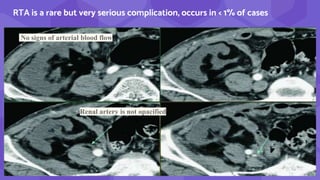

RTA is a rare but very serious complication, occurs in < 1% of cases

No signs of arterial blood flow

Renal artery is not opacified